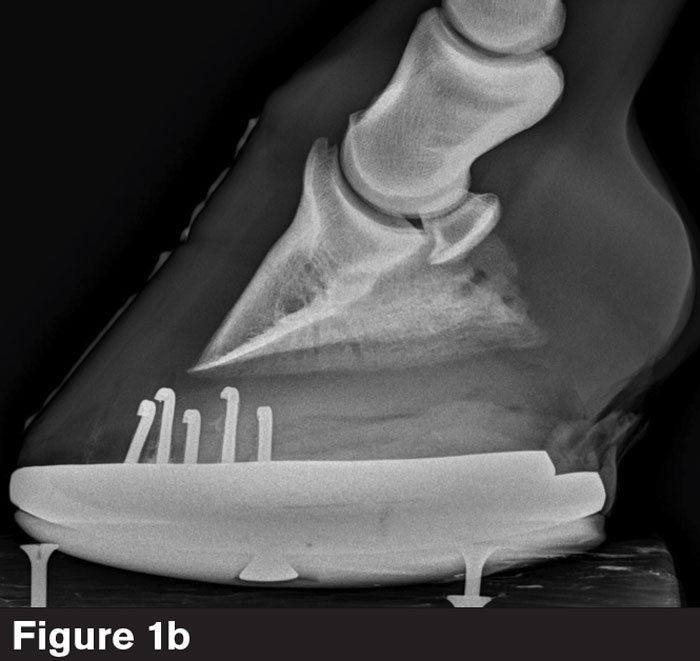

When an image captures two coffin bone wings (Figure 1b), one of three things could be occurring.

“You can have an asymmetrical coffin bone within a foot that’s actually balanced,” Barrett says. “You might have a medial-lateral imbalance. Or your beam is passing at too much of an angle underneath the bottom of the coffin bone.”

When two coffin bone wings and four screws are visible, as seen in Figure 1b, anatomical accuracy is in doubt.

“How do we measure sole depth?” he asks. “If the sole is superimposed by a wing of the shoe, we don't know where it ends. If you’re measuring the PA, a lot of times it will be different from one wing vs. the other. So, it’s crucial to get the soft tissue parameters on the bottom of the foot flat.”